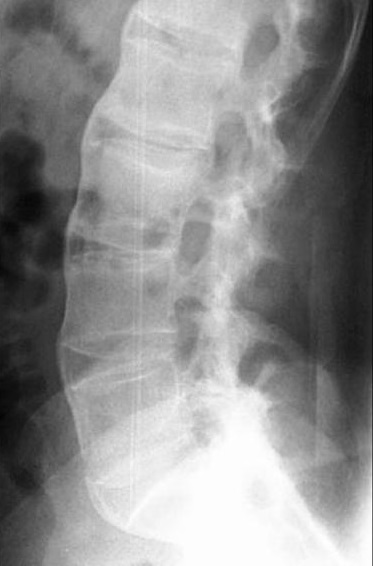

Aspect de fibrose , calcifiee du ligament

inter-epineuse posterieure et ligament para

vertebrale de L1-L5 en formation image de colonne de

bamboo ( bamboo spine ) |